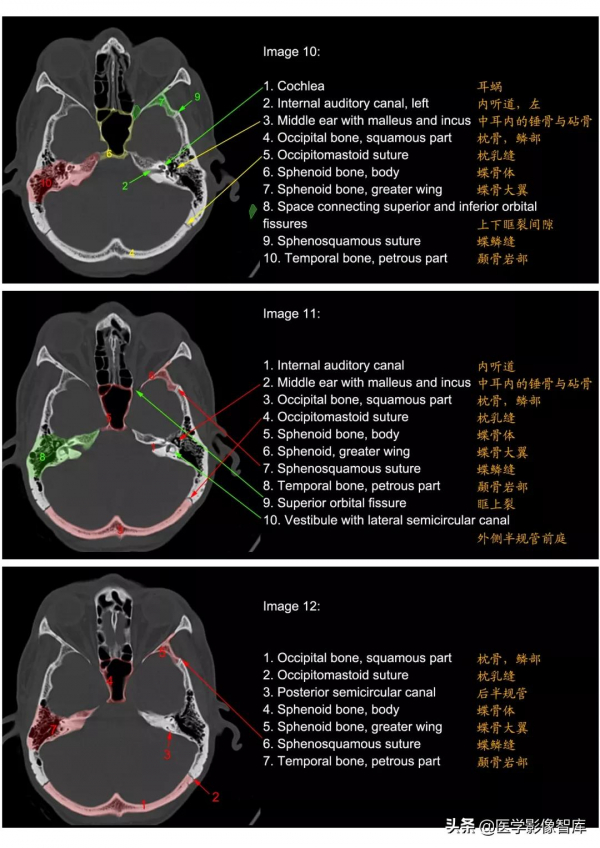

顱底

顳骨